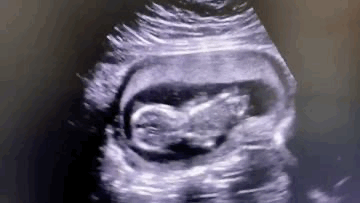

13 недель (кажется, ручкой трогает?)